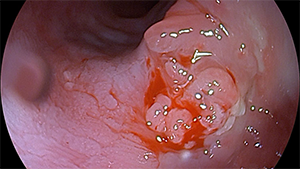

一个月后,李大娘如期而至,面色红润,步伐有力,看起来家属的肠内营养支持做得十分到位。复查胃镜,我们欣喜地发现,原瘘口部位呈瘢痕增生改变,取掉吻合夹后,没有再看到瘘口。仅仅一次治疗,一个月的时间,瘘口已经基本愈合了。我们叮嘱她,还要继续口服药物一段时间,仍然要避免过硬的食物,务必定期复查胃镜。